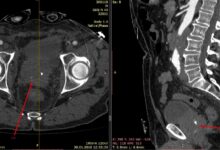

Маммография – это рентгенологическое исследование молочных желез, которое позволяет выявить изменения в их тканях, включая опухоли. Этот метод является основным способом скрининга рака груди у женщин.

Во время маммографии молочные железы сжимаются между двумя пластинами, чтобы получить более четкие изображения. Результаты исследования оцениваются радиологом на предмет наличия патологий.